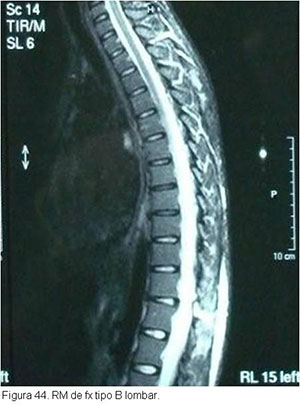

O tratamento seguirá o mesmo raciocínio discutido anteriormente, dependendo de quais estruturas estiverem lesadas. Particularidades da região toraco-lombar e lombar determinarão abordagens especificas caso a caso.(figuras 40, 41, 42 3, 44, 45)